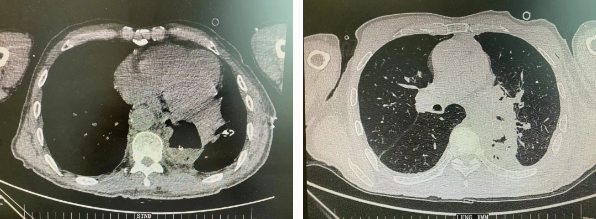

患者王某不幸同時患食管癌與左肺癌,病理類型系雙源發(fā)腫瘤,食管為鱗癌、肺為腺癌。食管癌和肺癌為胸外科最常見的疾病,但同時患兩種疾病,十分罕見。家屬輾轉(zhuǎn)多個醫(yī)院,得知李小飛院長擅長胸外科復雜手術(shù),慕名來西安國際醫(yī)學中心醫(yī)院。

經(jīng)過李小飛教授、李文海副教授、穆強副主任醫(yī)師團隊積極準備,排除手術(shù)禁忌;經(jīng)過全科術(shù)前充分討論,大家認為:如果分兩次進行手術(shù),另一種疾病勢必會受到影響,腫瘤可能進展。胸外科手術(shù)對呼吸循環(huán)影響較大,同期實施兩個手術(shù)更要小心謹慎。李小飛教授主持術(shù)前討論,設計合理手術(shù)方式,由于食管癌胸腔鏡手術(shù)為右側(cè)入路,但為兼顧左肺癌手術(shù),則采用傳統(tǒng)左開胸手術(shù)。

2022年4月25日,由李小飛教授主刀,同期行左側(cè)開胸:食管癌根治術(shù) 左肺癌根治術(shù),一次手術(shù)同時根治兩種惡性腫瘤疾病。經(jīng)過精細手術(shù)及術(shù)后管理,患者術(shù)后十天,恢復良好,進食良好,現(xiàn)已出院。